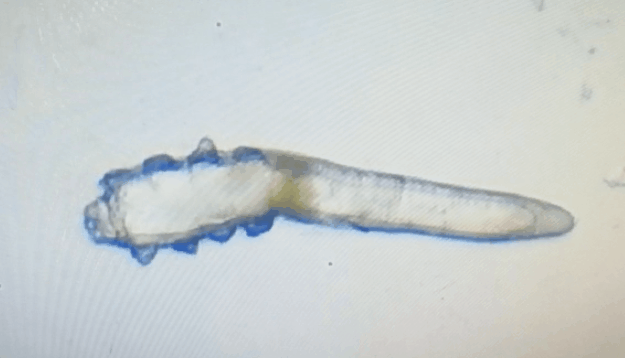

這就不得不提到眼科醫(yī)生經常使用的螨蟲檢測工具——螨蟲鏡檢。它通過顯微利器,無死角全方位掃描你的睫毛,讓螨蟲無處遁形。

林女士是一家公司的白領,常常需要濃妝出席各種會議,然而光鮮亮麗的背后,林女士的眼睛正遭受著和陳先生同樣的癥狀。在螨蟲鏡檢中,當看到自己的睫毛上爬滿了十幾只透明的生物-螨蟲,林女士嚇了一跳。幸而,經過廈門眼科中心干眼中心的治療,林女士解決了多年的眼睛干癢問題。